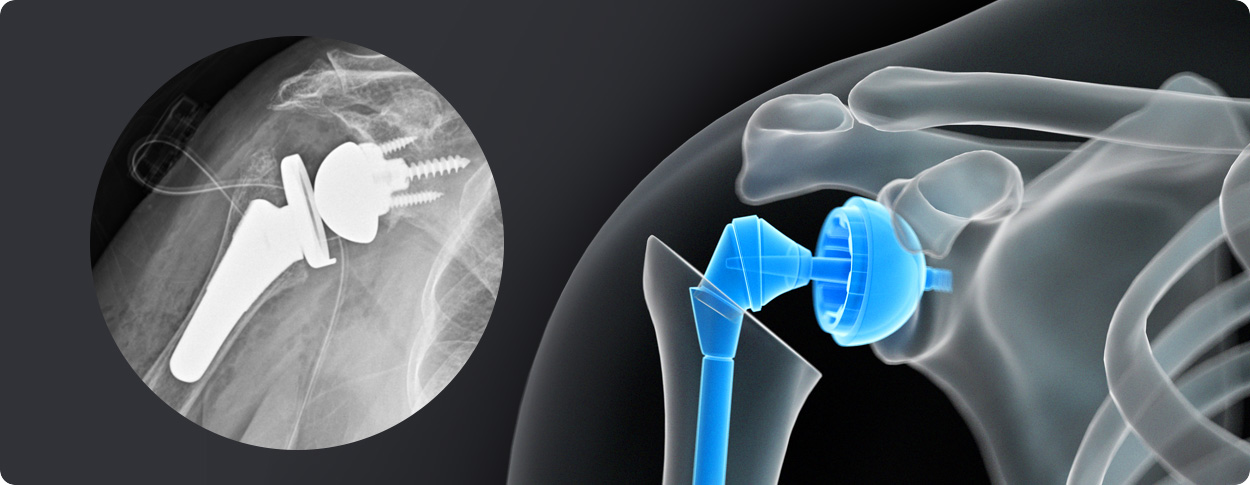

삼하게 망가져 거의 기능이 없는 관절을 제거한 후 특수하게 제작된 인공관절을 삽입하는 수술

비수술 치료에도 호전이 없는 경도의 관절염에서 시행합니다.

역행성 인공관절 전치환술

역행성 인공관절 진치환술

(회전근개 심한 파열 및 관절염 진행)